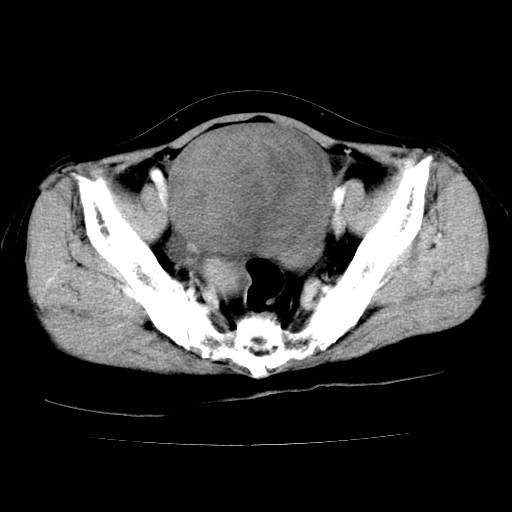

标题: CT24785:女,62岁,发现下腹部肿物半年。 [打印本页]

女,62岁,发现下腹部肿物半年,下腹部不适。

考虑子宫平滑肌肉瘤可能性大。

实性成分太多,要是囊腺瘤也要考虑恶性。